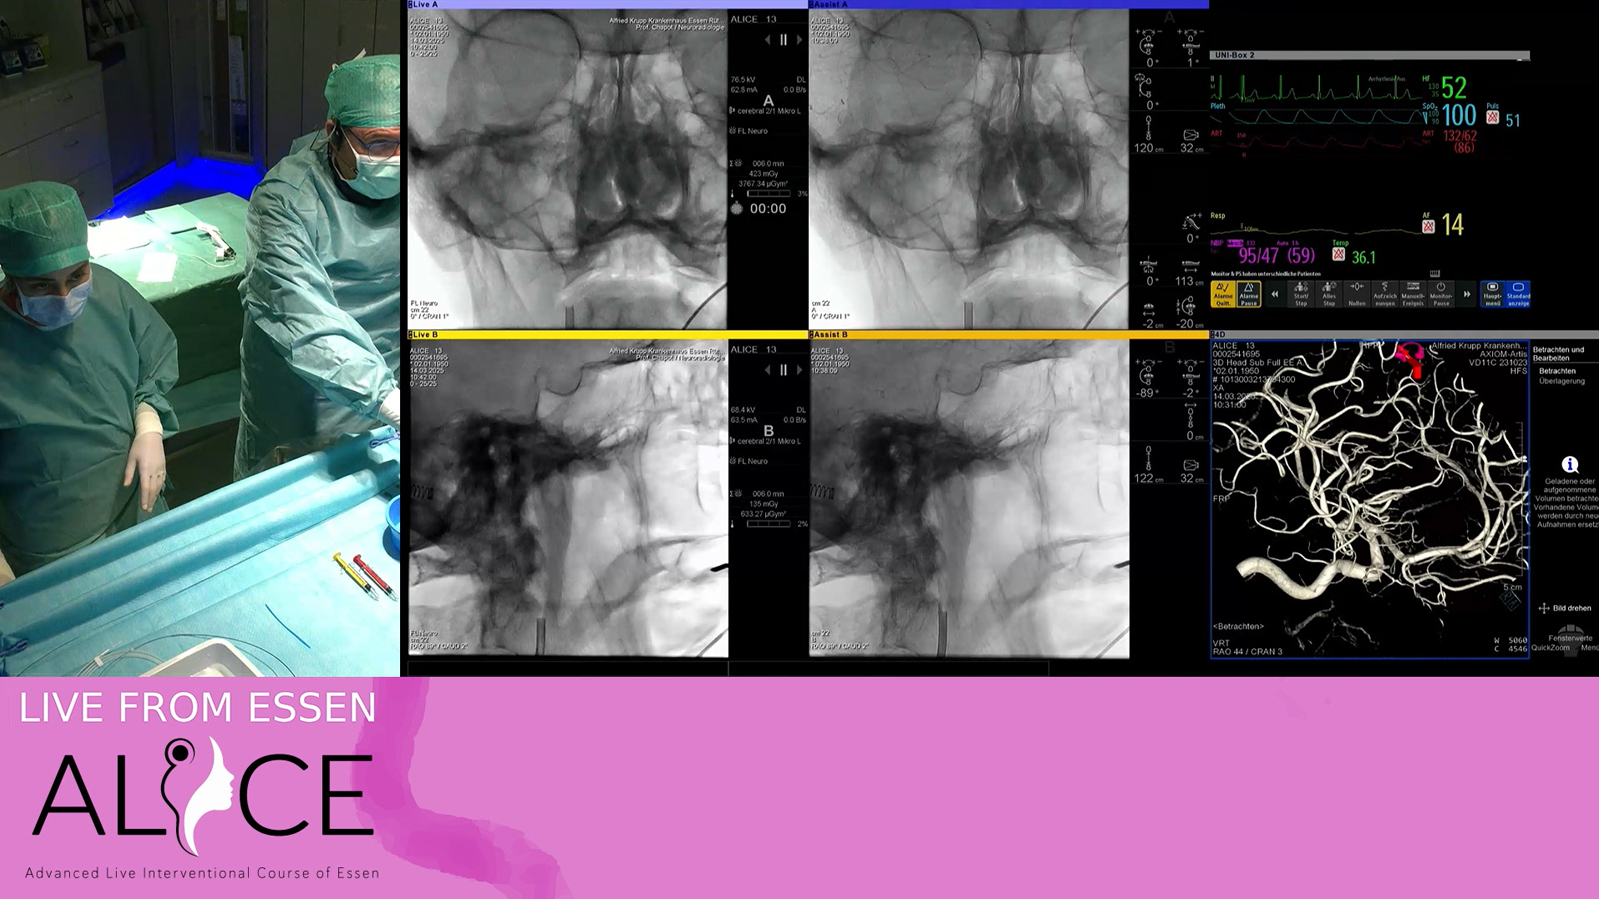

Extensive fast progressive Dural fistula treated by transvenous embolization with PHIL under double balloon protection of the sinus

Watch the video